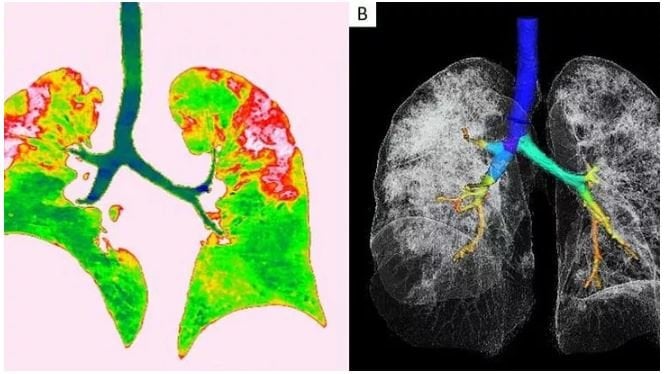

Radyologlar, tomografi görüntüleri sayesinde lezyonların dağılımının daha net anlaşılmasının, virüsü tanıma ve tedavisi için yapılan araştırmalarda önemli olduğunun altını çiziyor. Covid-19'dan kaynaklı zatürre hastası 54 yaşındaki bir kadının transversal ve koronal bilgisayarlı tomografi (BT) görüntülerinde pulmoner lezyonların üst lobda daha yaygın olduğu görülüyor.

Vuhan kentinden döndükten sonra bir hafta boyunca ateşi 38.5 dereceden düşmeyen kadına, nefes darlığı, öksürük ve halsizlik semptomlarıyla hastane yattıktan sonra Covid-19 testi yapıldı. Test sonuçları pozitif çıkan hastaya zatürre teşhisi kondu. Uygulanan tedaviyle söz konusu hastanın semptomlarının hafiflediği rapor edildi. Koronavirüsün akciğerlere verdiği zararı gösteren röntgen ve tomografi görüntüleri ortaya çıktı.